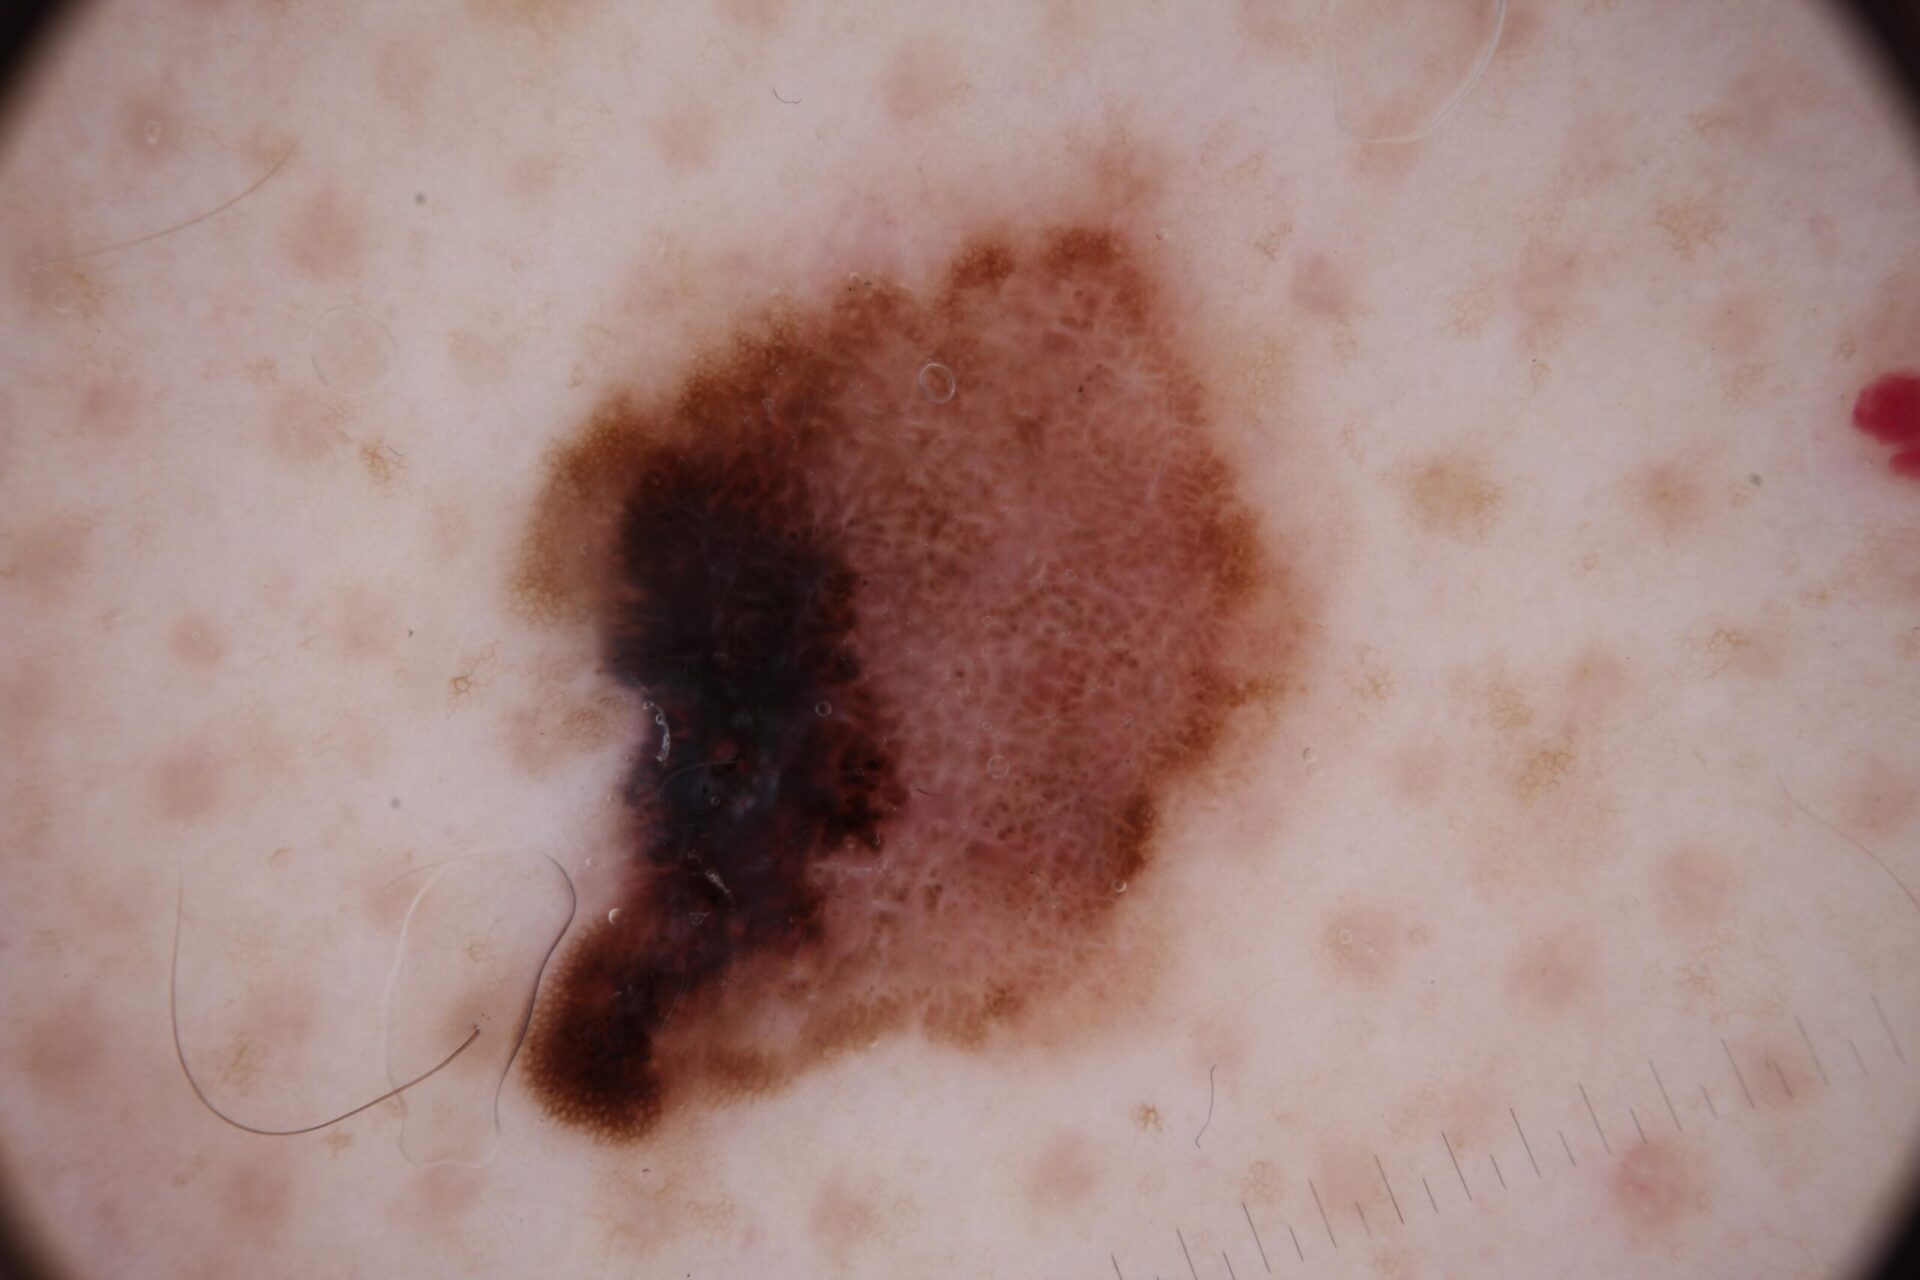

Melanoma Photos

Nodular melanoma on the leg of a Native American woman.

Photo: International Skin Imaging Collaboration

Amelanotic melanomas may be pinkish-looking, reddish, purple, normal skin color or essentially clear and colorless.